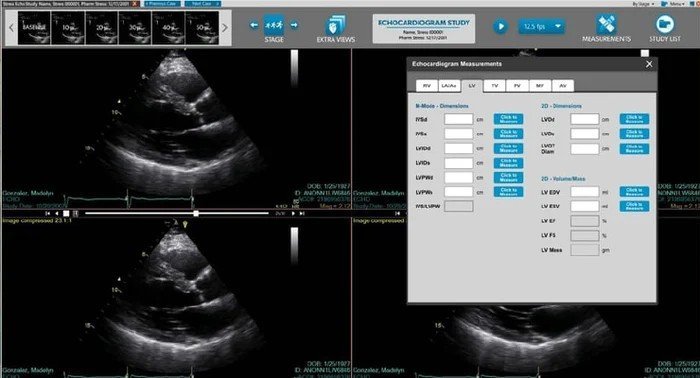

A look into the NovaCardio viewer

• Echocardiogram Study